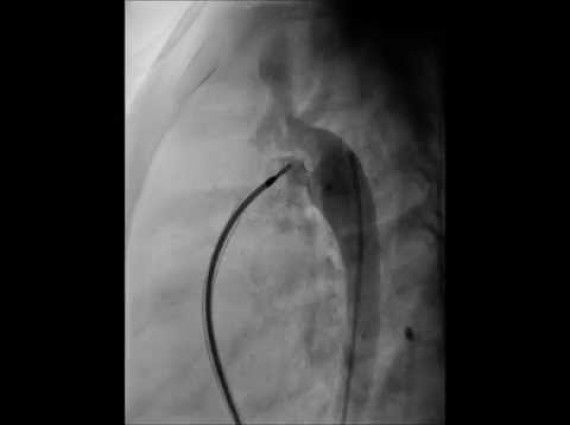

Son zamanlarda bazı doğuştan kalp hastalıklarının kesin tedavisinde, bazılarının palyatif tedavilerinde girişimsel tedavi yöntemleri ön plana çıkmıştır. Kalp kateterizasyonu / anjiyografi yöntemiyle uygulanan bir tedavi yöntemidir.

İşlemler cerrahiye göre kısa sürmekte, daha az komlikasyon ve daha az hastane kalış süreleri olmaktadır. Kalp durdurulmamakta, çoğunlukla herhangi bir kan transfüzyon ihtiyacı gerektirmemektedir. Vücutta herhangi bir kesi veya skar (ameliyat izi) oluşmamaktadır. Yoğun bakım ihtiyacı çok az vakada gerekmektedir. Kalpteki delikler, kapak yada damarlardaki darlıklar, suni kapak yerleştirmeleri dahil birçok işlem girişimsel tedavi yöntemiyle mükemmel bir şekilde uygulanabilmektedir. Birden fazla ve farklı patolojileri olan kalp hastalıklarında aynı seansta girişimsel tedavi uygulamaları gerçekleştirilebilmektedir.

Girişimsel tedavi seçenekleri ve çeşitliliği giderek artmakta doğuştan kalp hastalıklarının %80’ine uygulanabilmektedir.